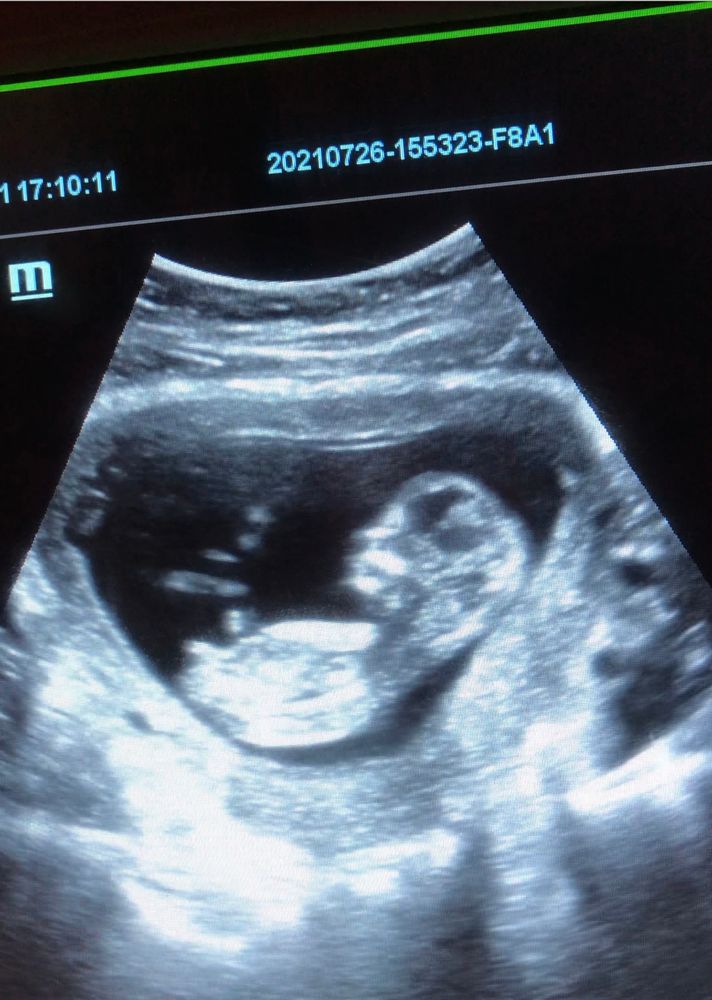

УЗИ, КТГ, доплерСегодня сходила на узи по определению пола, сказали, что будет девчуля,👧 гадания по методу Рамзи и половому бугорку на мне не сработали🤷🏻♀️ Завтра отправлюсь к другому узисту по показаниям, кровит с 13 недели. Думаю завтра уж точно будет известно, кто ж у нас в пузике💕

это фото, сделанное сегодня